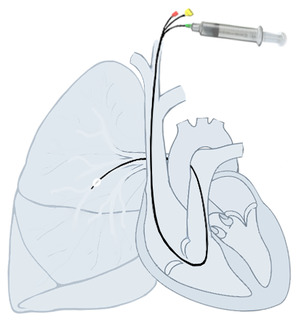

Right heart cath using a Swan-Ganz pulmonary artery catheter

Right heart catheterization (RHC) allows the physician to determine the pressures within the heart (intracardiac pressures). The heart is most often accessed via the internal jugular or femoral vein; arteries are not used. Values are commonly obtained for the right atrium, right ventricle, pulmonary artery, and pulmonary capillary "wedge" pressures. Right heart catheterizations also allow the physician to estimate the cardiac output, the amount of blood that flows from the heart each minute, and the cardiac index, a hemodynamic parameter that relates the cardiac output to a patient's body size. Determination of cardiac output can be done by releasing a small amount of saline solution (either chilled or at room temperature) in one area of the heart and measuring the change in blood temperature over time in another area of the heart.

Right heart catheterization is often done for pulmonary hypertension, heart failure, and cardiogenic shock. The pulmonary artery catheter can be placed, used, and removed, or it can be placed and left in place for continuous monitoring. The latter can be done an intensive care unit (ICU) to permit frequent measurement of the hemodynamic parameters in response to interventions.